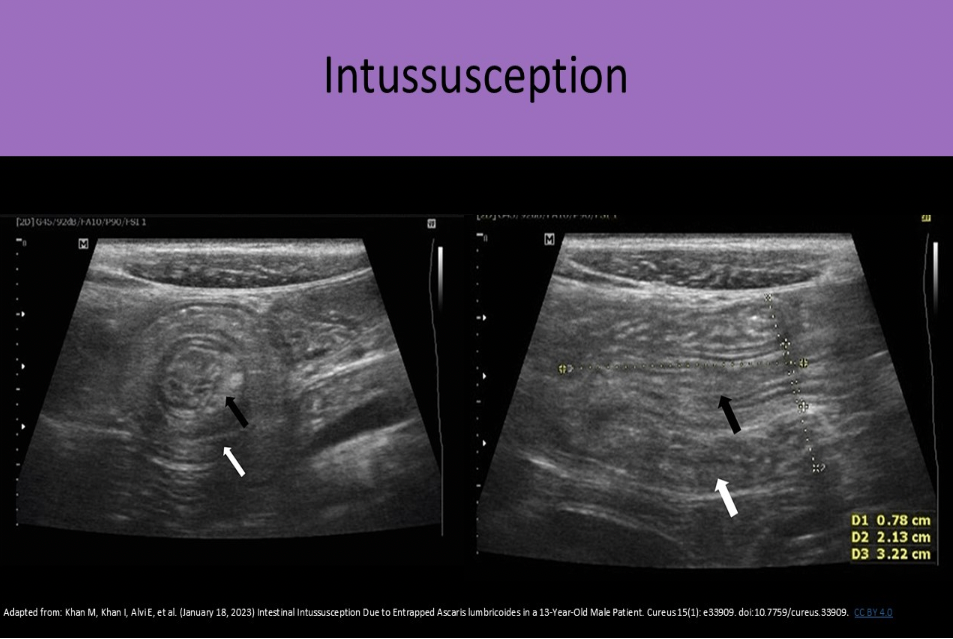

A 2yr old presents with a swollen abdomen and pain for 3 days. The doctor suspects an intussusception is present. How will this appear on the exam?

B. prominent focal area of concentric rings of bowel

An intussusception refers to a segment of bowel that involutes into itself. You will see a focal area of concentric rings of bowel that do not persitalse or change shape.

The term used to describe the involution of the small bowel upon itself is:

A. intussusception